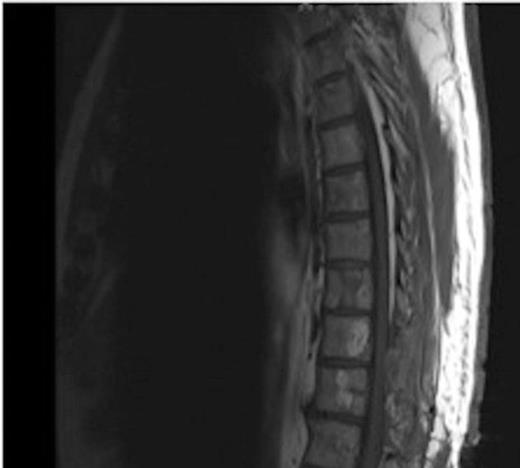

MRI showing the T10-11 extra-dural tumour with erosion of the T12 pedicle

On review of the original thoracic CT scan, which was performed 2 months prior to the MRI, the tumour was distinguishable but, as the spine is such a rare location for carcinoid metastasis, it was initially unreported.